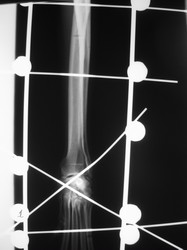

PRÁCTICAS CURSO DE FIJACIÓN EXTERNA PERFECCIONAMIENTO.

Artrodesis carpo.